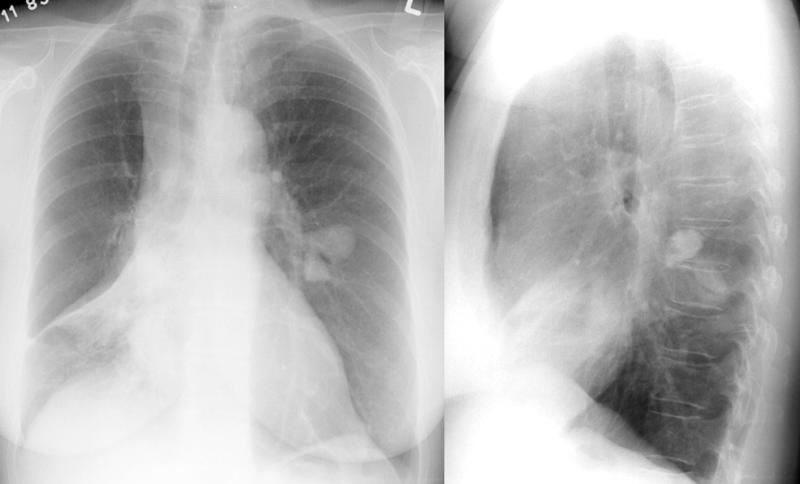

COPD

Asthma PA& Lat

Date: 06/06/2004